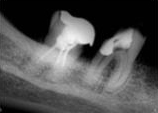

antes depois